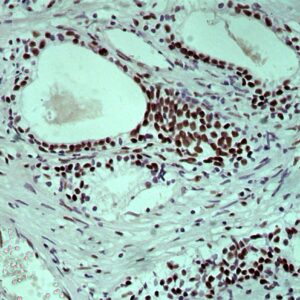

BioGenex has pioneered the development of miRNA research and diagnostics tools with leading-edge products. Currently, we offer over 240 ready-to-use (RTU) Super Sensitive™ Nucleic Acid (SSNA) miRNA ISH probes for accurate and early tumor diagnosis. These probes are sensitive enough to detect low-abundant miRNA(s) that are often required to identify biomarkers. They have a high melting temperature enabling stringent washes to remove non-specific binding. BioGenex miRNA probes are dual-end labeled with an anti-fluorophore to amplify the signal and yield clean and intense staining.